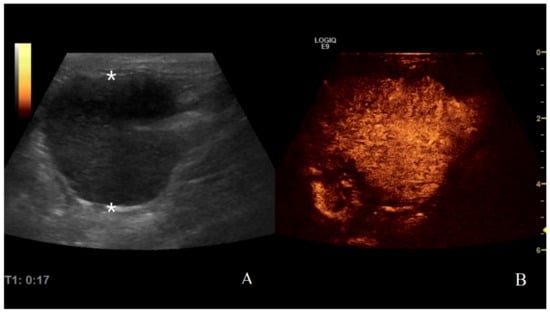

3.2. Analysis of B-Mode Examination

3.3. Analysis of CEUS Examination